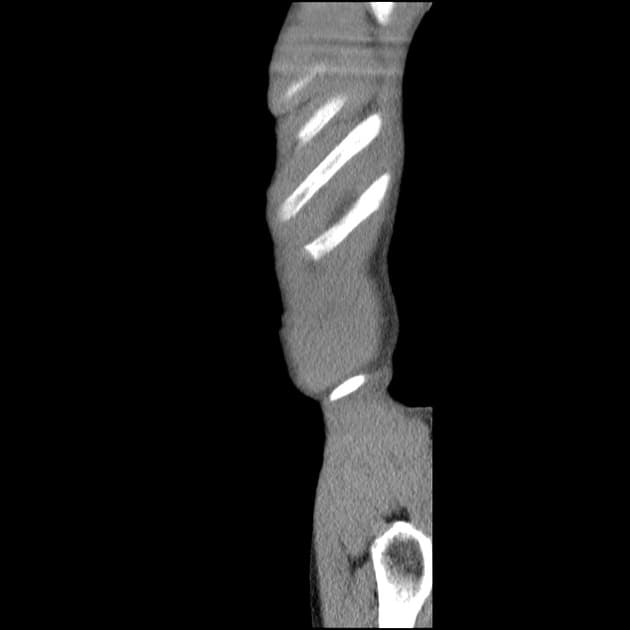

Cộng hưởng từ ruột (MRI enterography) phải dừng sớm khi phát hiện hình cản quang kim loại tại vùng chậu giữa và hố chậu trái.

Do hình cản quang kim loại, yêu cầu thực hiện MRI ruột được chuyển sang chụp cắt lớp vi tính (CT).

Chụp X-quang bụng không chuẩn bị (CT scanogram) cho thấy hình tăng tỷ trọng (metallic density) tại nửa bụng phải, cụ thể là ống nội soi dạng viên nang bị kẹt (trapped capsule endoscope). Hình ảnh này được xác nhận nằm trong lòng ruột (intraluminal), trong một quai hồi tràng.

Hình cản quang kim loại ban đầu xuất hiện ở vùng chậu giữa và hố chậu trái, nhưng thật đáng ngạc nhiên là ống nội soi bị kẹt lại nằm trong lòng ruột, bên phải, và có thể đã di chuyển trong quá trình làm MRI.